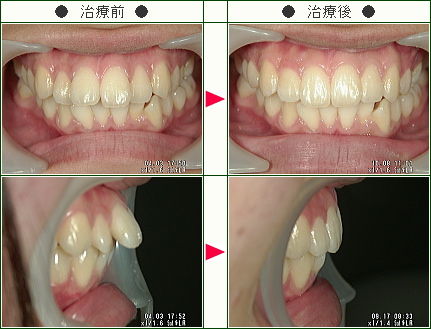

☆出っ歯矯正症例(古舘様 19歳 女性)

▼患者様の感想

私はずっと前歯が2本出ていることが悩みでした。

その他の歯並びは特に気になっていなかったので、前歯の部分矯正は私に合っていると思い、治療してもらう事にしました。

また、他の病院と比べて、歯を抜かない事や治療期間が短い事はとても魅力的でした。

治療している間は少しずつ歯並びが良くなっているのを感じることが出来てうれしかったです。

スタッフの皆さんもとても優しくて、特に担当している方には、些細な事でも気になる所を相談することが出来ました。

他の病院では治るまで2,3年かかると言われましたが、1年もかからず治ることが出来てとっても満足です。

南青山デンタルクリニックを選んで良かったです。

ありがとうございました。